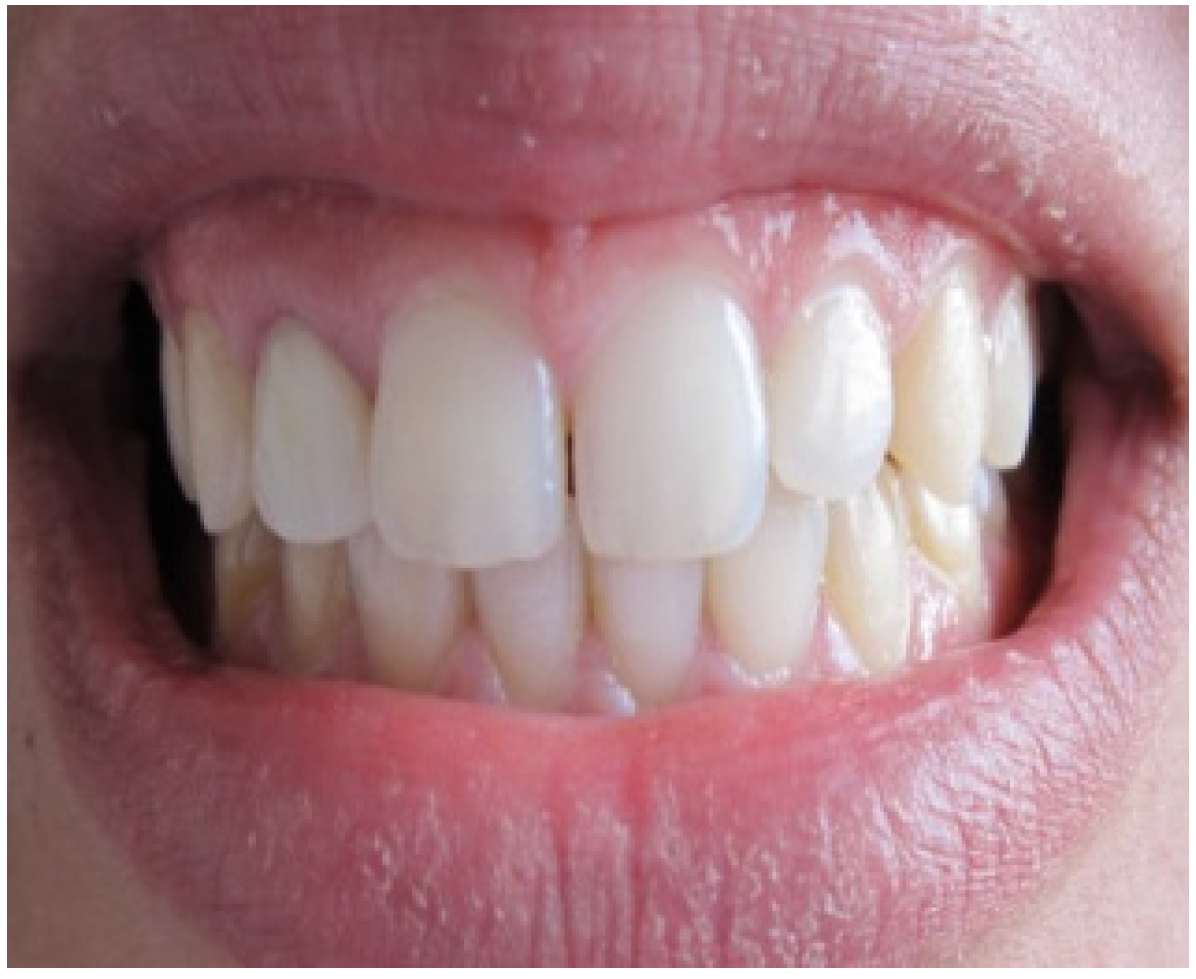

After 4 months of maturation, the abutment tooth was refined after placement and buildup of post and core materials (Figure 6). Later, a full arch impression was taken using a silicone material. An impression of the opposing dentition was also made with irreversible hydrocolloid. The shade was determined with the shade guide (VITA). The final restoration, Zirconia based crown, showing natural appearance with a correct gingival architecture was performed using the CAD/CAM technology. All of the team, including the prosthodontist, periodontist and the ceramist, were satisfied by the result—an aesthetic and functional restoration with a good marginal adaptation and an improved pink and white score (Figure 7). The most grateful of all was, however, our satisfied patient.

Figure 7. Final result showing an improvement of aesthetic appearance.